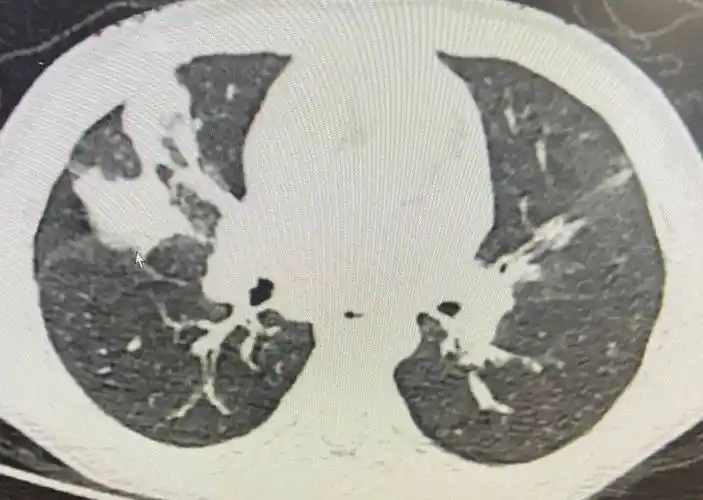

多图一文看懂大叶性肺炎的影像表现

右上叶实变后前位片即可看到一,肺叶或节段实变的影像学征象大叶性肺

血气正常.胸部ct:右肺上叶大叶性肺炎. 临床诊断:肺炎,大叶性.

【影像读片】大叶性肺炎?